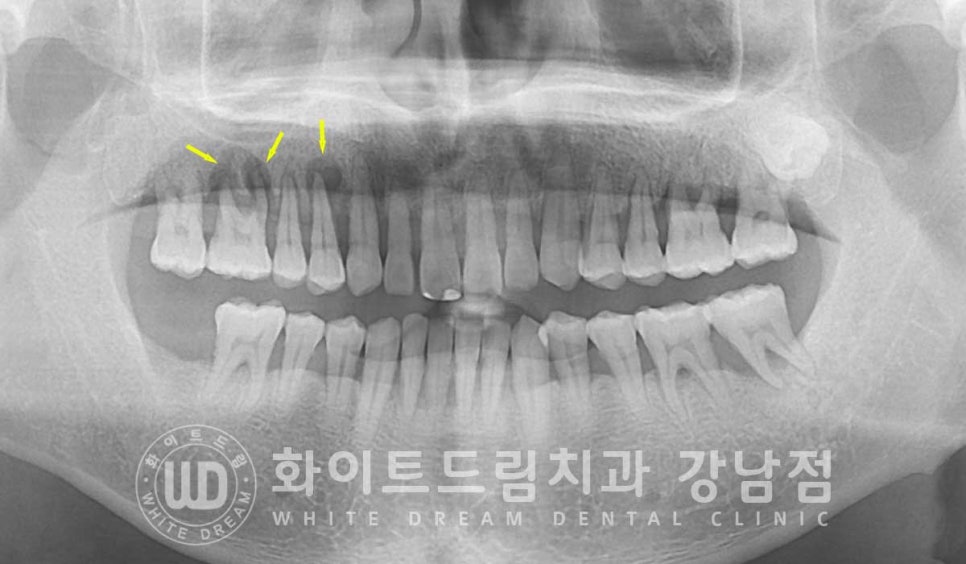

10번대 치아 주위 잇몸뼈를 보면 검은색으로

치아 뿌리 주위에 동그랗게 표기된 부분이 보일 겁니다.

x-ray 상에서 밀도가 낮을수록 이렇게 검은색으로 나타납니다.

원래는 잇몸뼈가 있어 하얗게 보여야 하는 부위인데

잇몸뼈가 녹고 그 자리에 액체(고름)이 차있는 상태라고 보시면 되겠습니다.